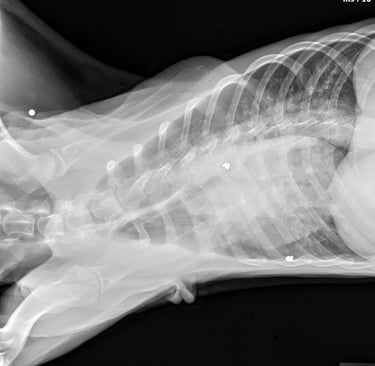

Cooper’s story is heartbreaking. He was found near the woods in Hilliard, painfully thin and carrying the scars of a cruel past. X-rays revealed he had been shot with BB guns, and four pellets are still lodged in his body.